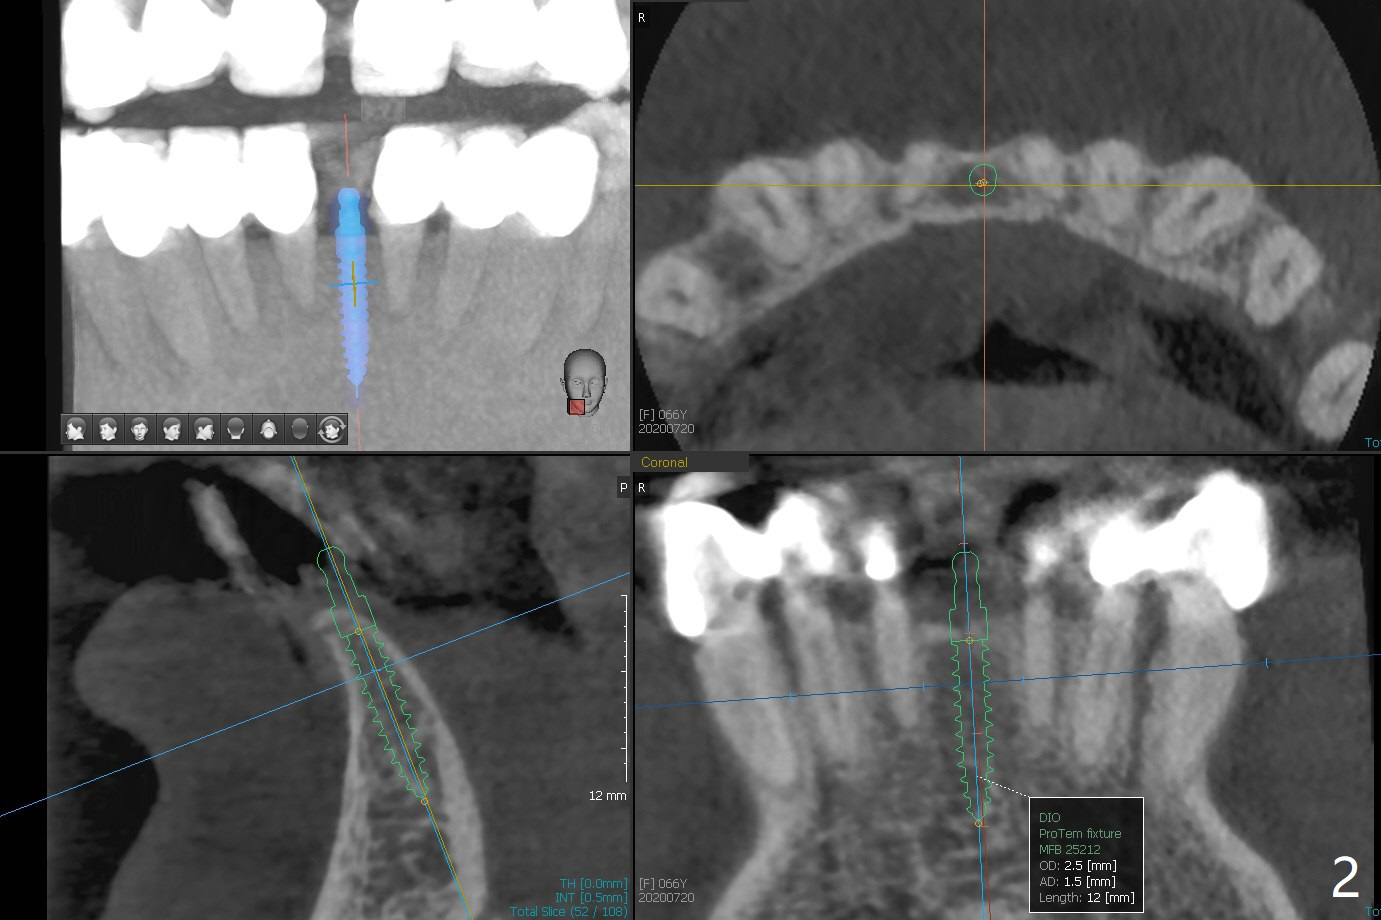

可以重做下颌7个连体牙冠,连接所有牙冠,中缝不再出现,但是费用高,口腔卫生不容易维持。简易办法是种植一个连体植体(1 -piece implant, 2.5x12(4) mm (直径,长度(袖),图二,图三(冠状截面))。 切口暴露狭窄牙槽嵴(图四),截除牙槽顶(图五黑色),然后在平坦骨面开始钻洞(图六红色箭头)。植体尽量种深点防止螺纹暴露,后期骨质密度容易增加。第一个钻头1.5x10毫米,拍摄根尖片,如果方位好,使用2x12mm, 2.5x6 mm钻头,或者2.5mm tap,植体植入。如果方位不好,纠正后,一定要有根尖片证实,才能用下一个钻头。牙槽嵴截除处骨质密度~700单位(图七),不是很高,放置植体前不必用同等大小钻头或者tap。